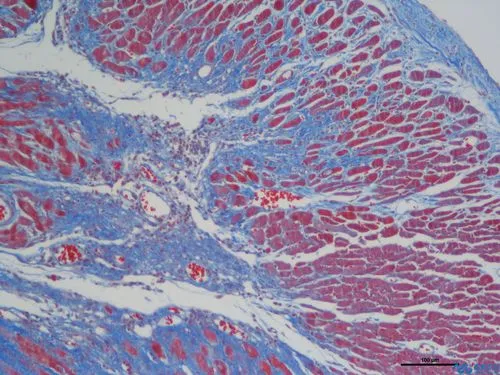

完成以上步驟后,切片中的膠原纖維、黏液和軟骨將呈現藍色(如果使用淺綠色液體,則呈現綠色),細胞質、肌肉、纖維素和神經膠質將呈現紅色,而細胞核將呈現黑色藍色。